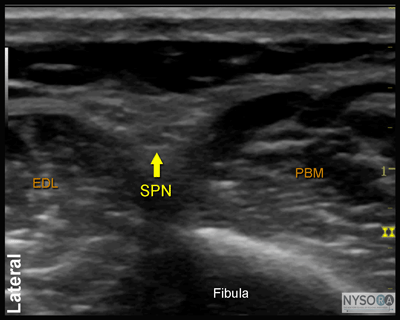

Figure 7:Transducer position and needle insertion to block the superficial peroneal nerve. ![]() Figure 8: Cross-sectional anatomy of the superficial peroneal nerve (SPN). EDL, extensor digitorum longus muscle; PBM, peroneus brevis muscle. Superficial Peroneal Nerve The superficial peroneal nerve innervates the dorsum of the foot. It emerges to lie superficial to the fascia 10 to 20 cm above the ankle joint on the anterolateral surface of the leg. A transducer placed transversely on the leg, approximately 5 cm proximal and anterior to the lateral malleolus, will identify the hyperechoic nerve lying in the subcutaneous tissue immediately superficial to the fascia (Figures 7, 8, and 9A and B). If the nerve is not readily apparent, the transducer can be traced proximally on the leg until, at the lateral aspect, the extensor digitorum longus and peroneus longus muscles can be seen with a prominent groove between them leading to the fibula (Figure 10A and B). The superficial peroneal nerve is located in this intermuscular septum, just deep to the fascia. Once it is identified at this more proximal location, it can be traced distally to the ankle. Because the superficial nerves are rather small, their identification with ultrasound is not always possible in a busy clinical environment. Sural Nerve The sural nerve innervates the lateral margin of the foot and ankle. Proximal to the lateral malleolus, the sural nerve can be visualized as a small hyperechoic structure that is intimately associated with the small saphenous vein (Figures 11, 12, and 13A, B). A calf tourniquet can be used to increase the size of the vein, aiding in identification of the nerve. Saphenous Nerve The saphenous nerve innervates the medial malleolus and a variable portion of the medial aspect of the leg below the knee. The nerve travels down the medial leg alongside the saphenous vein. Because it is a small nerve, it is best visualized 10-15 cm proximal to the medial malleolus, using the saphenous vein as a landmark (Figures 14, 15, and 16A, B). A proximal calf tourniquet can be used to assist in increasing the size of the vein. The nerve appears as a small hyperechoic structure.

Figure 10: (A) Ultrasound anatomy of the superficial peroneal nerve. (B) Ultrasound anatomy of the nerve with structures labeled. EDL, extensor digitorum longus muscle; PBM, peroneus brevis muscle; SPN, superficial peroneal nerve.